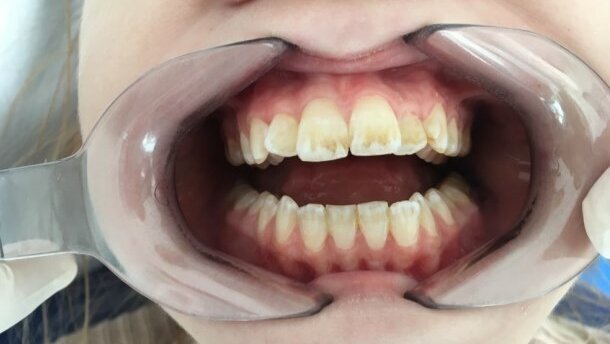

Wielu autorów analizowanych prac kwalifikuje chorych z CF do grupy wysokiego ryzyka rozwoju chorób jamy ustnej, w tym próchnicy, podając jako główne przyczyny redukcję wydzielania śliny, wzrost kolonizacji jamy ustnej paciorkowcami z grupy Streptococcus mutans oraz innymi bakteriami próchnicotwórczymi, a także defekty w budowie szkliwa, chorobę refluksową przełyku, stosowanie diety wysokokalorycznej i stałe przyjmowanie wysokowęglowodanowych medykamentów.12,13 Często występujące stomatologiczne dolegliwości obserwowane u chorych na CF obejmują defekty i przebarwienia szkliwa.14

Wydaje się, że na rozwój tych zaburzeń wpływa białko CFTR, regulujące poziom mineralizacji i pH szkliwa,14-16 oraz antybiotykoterapia z grupy tetracyklin i karbapenemów. Wg Peker i wsp. stałe przyjmowanie antybiotyków może wpływać na ograniczenie liczby bakterii w jamie ustnej, w szczególności gatunku Streptococcus mutans, odpowiadających za próchnicę. W prowadzonych badaniach wykazali oni, że długotrwała antybiotykoterapia może być inhibitorem rozwoju biofilmu bakteryjnego w jamie ustnej, a tym samym wpływać na redukcję odsetka przypadków próchnicy.12 Warto jednak podkreślić, iż na obserwowany efekt ograniczenia liczby patogenów może mieć również wpływ znaczna świadomość i większe zaangażowanie w czynności higieniczne jamy ustnej chorych na mukowiscydozę.

Na zaburzenia w układzie pokarmowym i oddechowym u chorych z mukowiscydozą mogą mieć również wpływ w przyzębiu, jednak i w tej kwestii badacze przyjmują różne stanowiska. Dąbrowska i wsp. twierdzą, że ze względu na częste infekcje górnych dróg oddechowych, pacjenci z CF często przyjmują ustny tor oddychania, co predysponuje do występowania zapalenia przyzębia oraz zapalenia błony śluzowej jamy ustnej.13 Ferrazzano i wsp. wykazali również większą ilość kamienia nazębnego u dzieci chorych na CF, zwykle na powierzchni dolnych przednich zębów. Może to wynikać z podniesionego poziomu wapnia w ślinie obserwowanego u tych chorych.3,17,18 Wyniki badań prowadzonych przez zespół Aps i wsp. nie potwierdzają jednak takich obserwacji19, wskazują natomiast na obniżenie stanów zapalnych i krwawienia dziąseł oraz zmniejszoną zdolność odkładania się złogów i płytki nazębnej (Ryc. 3).13,17,18 Znaczący wpływ na dobry stan tkanek przyzębia mogą mieć enzymy trzustkowe, przyjmowane przez chorych, które zapobiegają precypitacji fosforanu wapnia.14